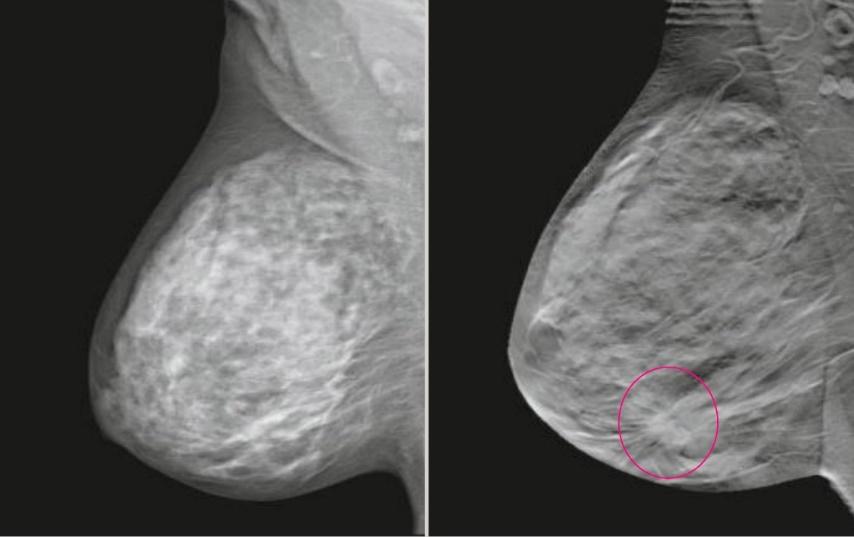

Томосинтез - это реконструктивный рентгенологический метод исследования, представляющий собой последовательность томограмм, произведенных на заданную глубину с фиксированным расстоянием между ними. Цифровой томосинтез (DBT) использует возможности трехмерной маммографии для получения и анализа срезов, что позволяет удалить близлежащие ткани и повысить качество диагностики, особенно при плотной ткани молочной железы.

Пример сравнения классической маммограммы и томосинтезного среза

FFDM (2D) / BTM (3D)

Цифровой томосинтез, или 3D маммография, часто используется вместе с классической 2D маммографией для обследования плотных молочных желез или в качестве дополнительного метода при обнаружении патологий. Основным показанием для выполнения 3D маммографии является высокая плотность молочных желез (ACR C и D). В таких случаях может быть проведена маммография как в 2D, так и в 3D режимах в качестве основного метода обследования для пациентов старше 40 лет. В редких случаях томосинтез может быть использован после маммографии у женщин с низкой плотностью молочных желез для дополнительной диагностики, например, при подозрении на опухоль в молочной железе.